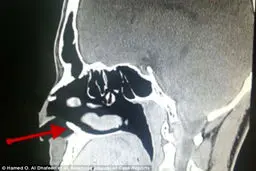

• خارج کردن دندان از حفره بینی+ تصاویر

خارج کردن دندان از حفره بینی+ تصاویر